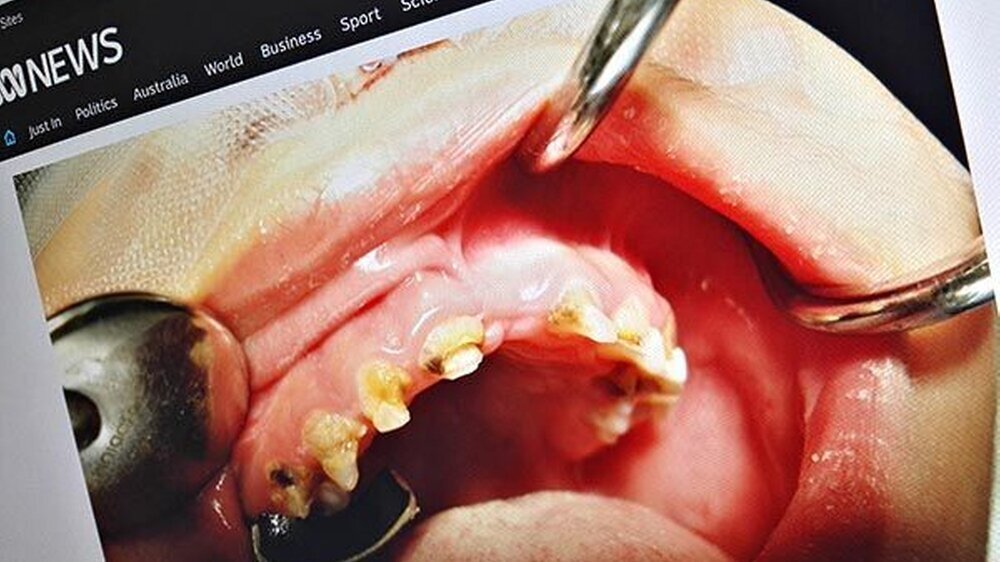

Australien: ECC nimmt deutlich zu

Zahnarzt Dr. Mark Penrose vom South Australien Dental Service, bezeichnete die Lage gegenüber

ABC News

als alarmierend und frustrierend, angesicht der Tatsache, dass die Fälle einzig auf stark zuckerhaltige Nahrung und mangelnde Mundhygiene zurückzuführen seien.

Es sei nicht ungewöhnlich, bis zu 12 oder 14 Zähne bei Kindern extrahieren zu müssen, die gerade einmal drei oder vier Jahre alt sind, berichtet auch Dr. Sophie Beaumont vom Royal Dental Hospital in Melbourne.